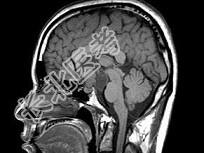

- 单项选择题男,27岁, 头痛、双眼视力下降、多饮、多尿4个月,根据所提供图像, 最可能的诊断是 ( )

A、颅咽管瘤

B、垂体瘤

C、生殖细胞瘤

D、胶质瘤

E、神经鞘瘤